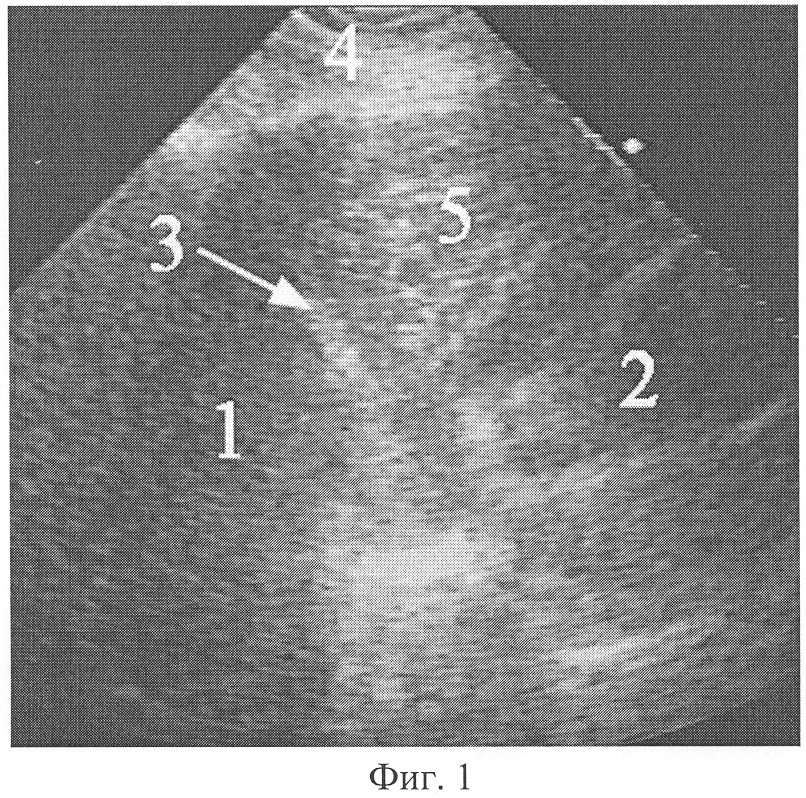

Фиг.2. Эхограмма целомической кисты перикарда при поперечном сканировании справа парастернально из межреберья над местом прикрепления реберной дуги к грудине.

На фиг.2 обозначено: 1 – печень, 2 – сердце (лоцируется нечетко при движении), 3 – медиальная поверхность правого купола диафрагмы, 4 – мягкие ткани грудной стенки, 6 – целомическая киста перикарда, 7 – капсула целомической кисты перикарда.